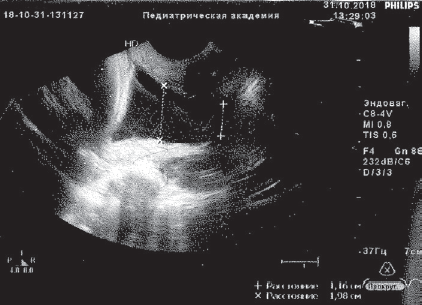

The report presents two clinical observations of pregnancy outcome in patients with isthmic-cervical insufficiency of functional (first observation) and functional-organic (second observation) origin. In both cases, previously treated cervical erosion by laser (in the second observation – carried out excision of the cervix). In secundiparous women in the present pregnancy were noted recurrent urogenital (first observation) and genital (second observation) infection with a threatened miscarriage and the need for re-hospitalizations. Complex therapy with the introduction of obstetric discharge pessarium was not effective enough, there were manifestations of the inflammatory response of the body, isthmic-cervical insufficiency progressed, up to prolapse of the fetal bladder into the cervical canal (first observation). When entering the perinatal center, the treatment of pregnant women included methods of low-volume membrane plasmapheresis and photomodification of blood with ultraviolet and laser rays (alternated). In both cases, it was possible to stop the manifestations of inflammatory response, to improve the condition of the cervical canal, to prolong pregnancy to the term of normal childbirth. In the first observation, the birth occurred naturally, in the second case cesarean section was performed due to organic changes in the cervix. Childbirth, the postpartum period in women proceeded normally. Children were born healthy, full-term, develop normally, receive breastfeeding.